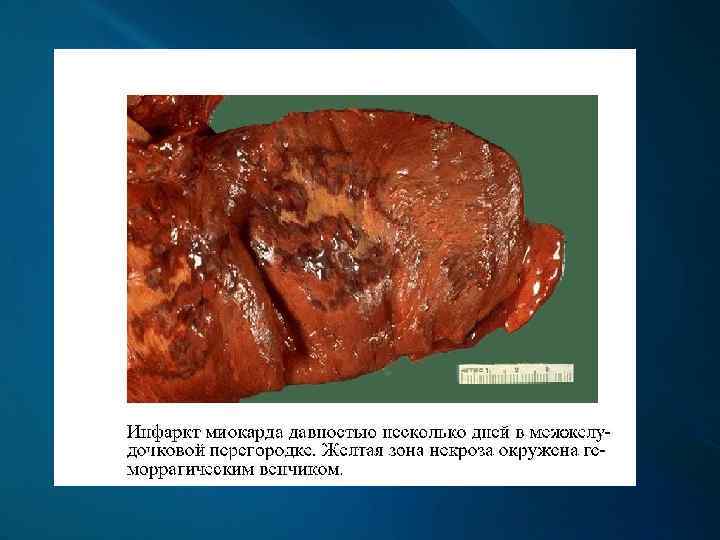

Макроскопически: первые часы - миокард дряблый, неравномерно кровенаполнен; через 18 -24 ч. – четко виден некроз; конец 1 -х сут. – некроз глинистокрасноватый, выбухает из-за отека, с геморрагическим венчиком; к 4 -6 сут. и далее – некроз западает, плотный, желто-серый, с красной каймой грануляционной ткани вокруг; через 3 -5 нед. – рубец красновато-серый, затем белесовато-серый.